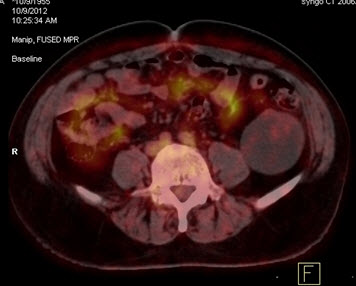

Hình 5. Bệnh nhân Nguyễn X.T., nam, 58 tuổi. Chẩn đoán: U lympho ác tính không Hodgkin, giải phẫu bệnh: WF6. Hình PET cho thấy tổn thương ở phổi, hạch, xương, tuyến thượng thận hai bên (mũi tên). Hình CT và PET/CT cho thấy tổn thương tăng hấp thu FDG tại vị trí tuyến thượng thận hai bên (mũi tên), max SUV=11,34.